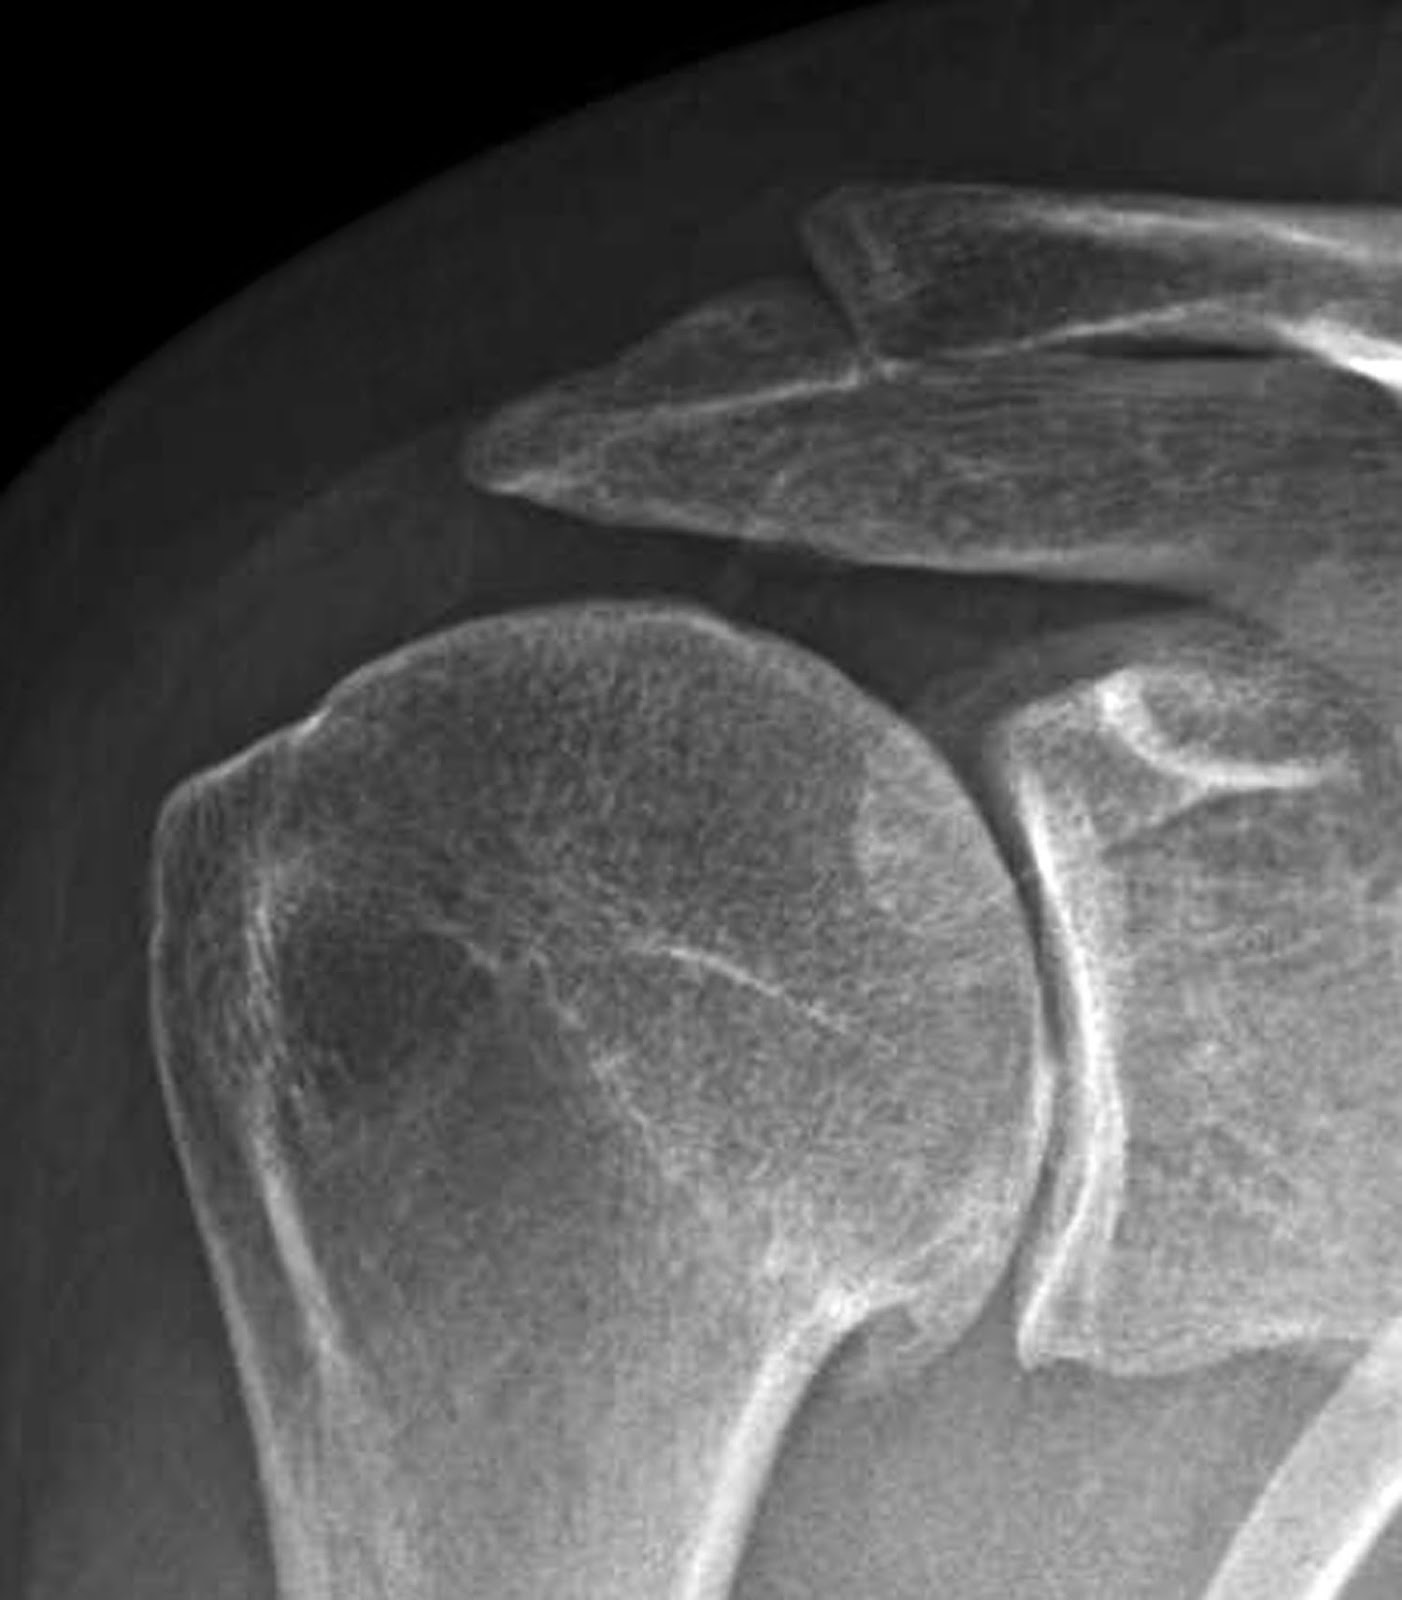

Shoulder Joint X Ray Interpretation . This view reveals the joint gap and the vertical. The shoulder series is fundamentally composed of two orthogonal views of the glenohumeral joint including the entire. Mri is best for evaluating soft tissue structures and evaluating bone contusions or trabelcular microfractures. Shoulder radiographs are often the only imaging exam necessary for the evaluation of acute shoulder trauma, calcific tendonitis,. The body has to be rotated about 30 to 45 degrees towards the shoulder to be imaged, and the standing or sitting patient lets the arm hang. Healthcare providers use a shoulder x.

The shoulder series is fundamentally composed of two orthogonal views of the glenohumeral joint including the entire. Shoulder radiographs are often the only imaging exam necessary for the evaluation of acute shoulder trauma, calcific tendonitis,. Mri is best for evaluating soft tissue structures and evaluating bone contusions or trabelcular microfractures. This view reveals the joint gap and the vertical. Healthcare providers use a shoulder x. The body has to be rotated about 30 to 45 degrees towards the shoulder to be imaged, and the standing or sitting patient lets the arm hang.